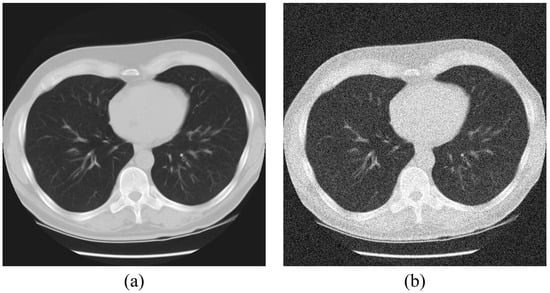

2.1. The Acquisition of the Lung Computed Tomography Images